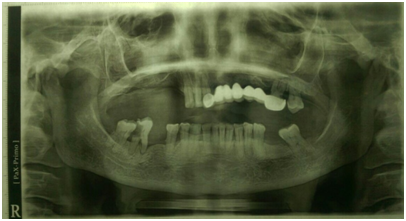

Over 60 year-old Sudanese woman knowledgeable with jaw problems initiate 12 months ago with spontaneous deep pain in the maxilla at the buccal left side. Her dentist referred her to the department of Oral Surgery, Khartoum Teaching Dental Hospital, when he identifies an extended exposed bone with pus discharge. The patient mentioned that over the 7 preceding months, she developed severe pain combined with episodes of swelling in the palate, discharge from bridge in left side of the upper jaw that extend from the upper central incisors to the first permanent molar in addition to halitosis.10 The past medical history she is adiabatic; had breast cancer and experience a wide local excision and auxiliary clearance 3 years ago. A six cycle chemotherapy regime was given since 2012. And 7 months ago bone scan confirmed skeletal metastasis in the vertebral column (Figure 1) and 12 cycle chemotherapy regime was given on 2016 (Zometa 4mg/month) intravenously.11 The intraoral examination revealed; marked halitosis, swelling in the palate which tender and discharge (blood + pus) on pressing, mobile bridge, mobility grade 3 in 26 and a large bony defect (yellowish exposed bone) in the upper left quadrant of the maxilla mainly involving the buccal alveolus under bridge (Figure 2). No extra oral findings were detected. Orthopantomogram view showed detected an osteolytic region in the maxilla left side (Figure 3) and C.T scan detected left maxillary mucosal thickening with nasal mucosal thickening (Figure 4). Incisional biopsy under local anesthesia was carried out with a segment of palatal mucosa adjacent to the necrotic bone.12 The pathology report showed only (mucositis) inflammation with no evidence of ulceration or neoplasia. Ciprofloxacin 500mg was prescribed for one month together with Chlorhexidine mouth wash. An isolation of the sequestrum, with mobility of the 26 tooth was obtained. It was decided to remove the left maxillary first molar and sequestrum conservatively.

Figure 3 (Panoramic view showing the extension of lesion in the maxillary left side).